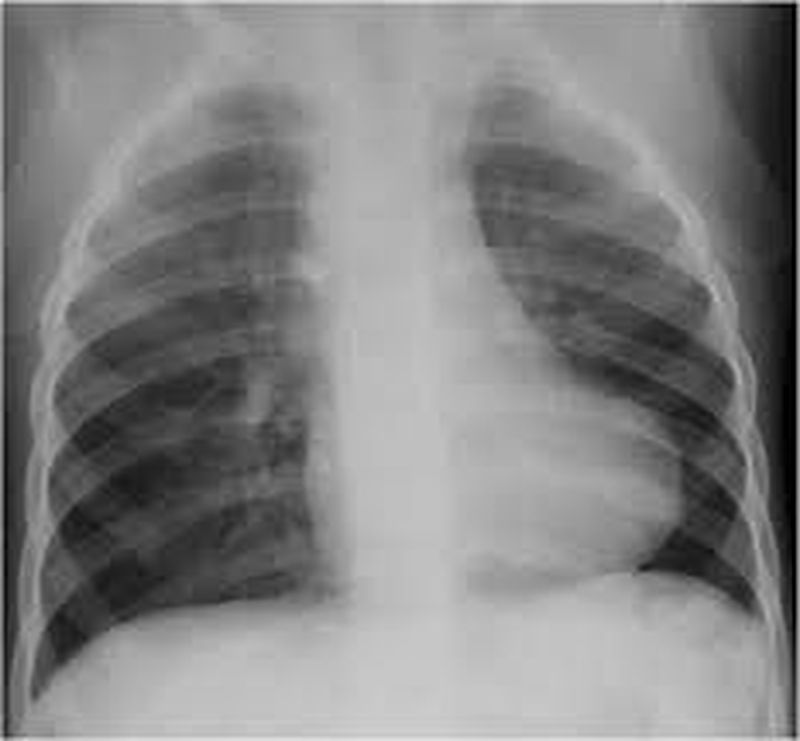

A child was brought in with complaints of chest pains, an x ray was done as shown above

TOF? ( Boot shaped heart)

Tetralogy of Fallot

RVE? cardiomegaly- Apex outward